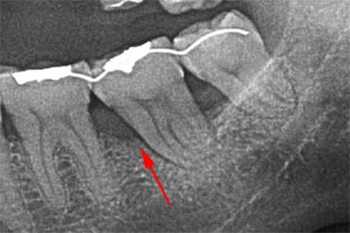

この症例では、歯間部の歯槽骨は骨吸収によって失われ、3mm程度の浅い骨縁下欠損を認めました(矢印)。

歯と歯の間の骨が無くなっているのが解りますか?

見た目には解りにくいですが歯茎から膿が出て腫れています。

エムドゲインを使用し歯と歯の間の垂直的硬組織の再生に成功したケースです。

術中である左の写真で、無くなっていた歯と歯の間の骨が再生しかけているのがおわかりいただけるでしょうか?

向かって右の術後の写真では完全に再生されました。

術後6年経過した現在も、膿漏の再発も無く予後は安定しています。